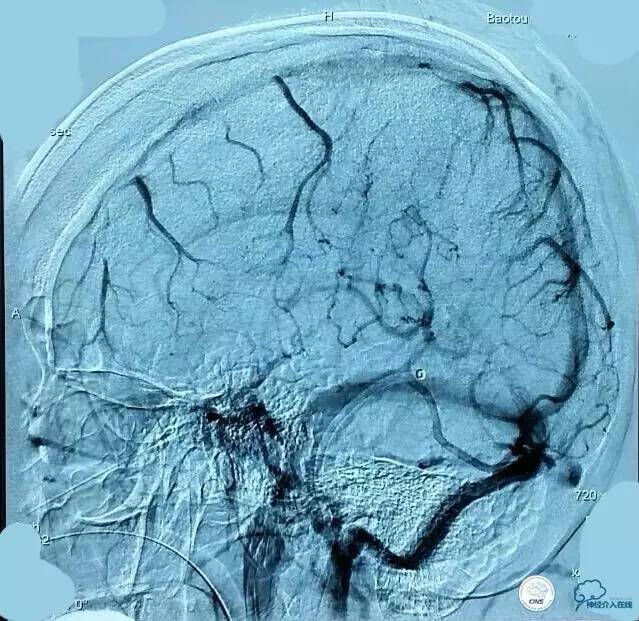

▼第三次取栓后造影,窦通畅,下矢状窦显影延迟,说明上矢状窦通畅了。